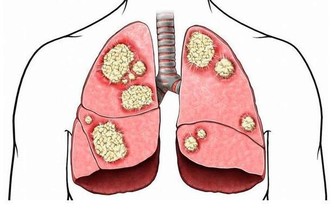

大量資料表明,吸煙與酗酒是腦卒中發病的最重要誘發因素。每天抽煙10~20支,腦卒中的發病率高於不吸煙者兩倍;每天抽20~30支,腦卒中的發病率高於不抽煙者5倍;而戒菸兩年後,發病危險就能降至與不吸煙者相似。另外,喝烈酒、猛喝酒、喝醉酒等不良習慣,很容易成為誘發腦卒中發作的“導火索”。